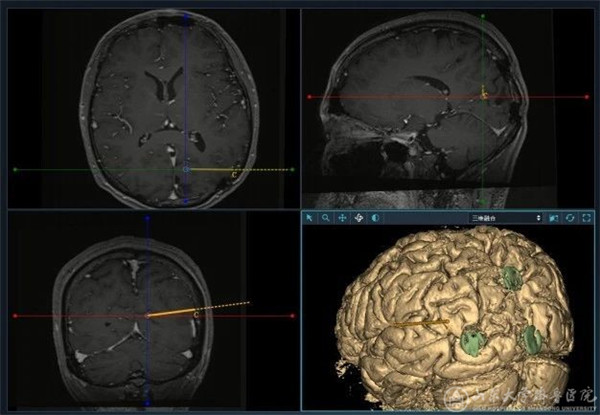

对药物难治性癫痫而言,如能够准确定位致痫灶并进行切除性手术,术后患者无发作率可达60-80%,因此术前评估一直是癫痫综合治疗的重点与难点。现阶段,对致痫灶的定位主要通过症状学、神经电生理、影像学及PET-CT等无创手段进行。如果上述手段无法准确致痫灶位置及范围,则有必要引入SEEG等有创诊疗技术。SEEG技术将定位手段从颅外引入颅内,从平面引向立体,可直接将电极放置至异常脑沟沟底、大脑内侧面、颅底、海马-杏仁核等常规皮层电极无法达到的部位,对大脑进行全方位立体化覆盖,从而准确定位病灶并判断致痫网络。在神经外科外科副主任、癫痫诊疗中心主任徐淑军教授带领下,癫痫诊疗中心外科团队先后完成了省内首例SEEG电极植入、机器人辅助SEEG植入及无框架SEEG 植入等手术,是目前省内完成SEEG手术台数最多,植入电极根数最多的单位,术后无颅内出血、感染等严重并发症,取得了良好的疗效及患者满意度。